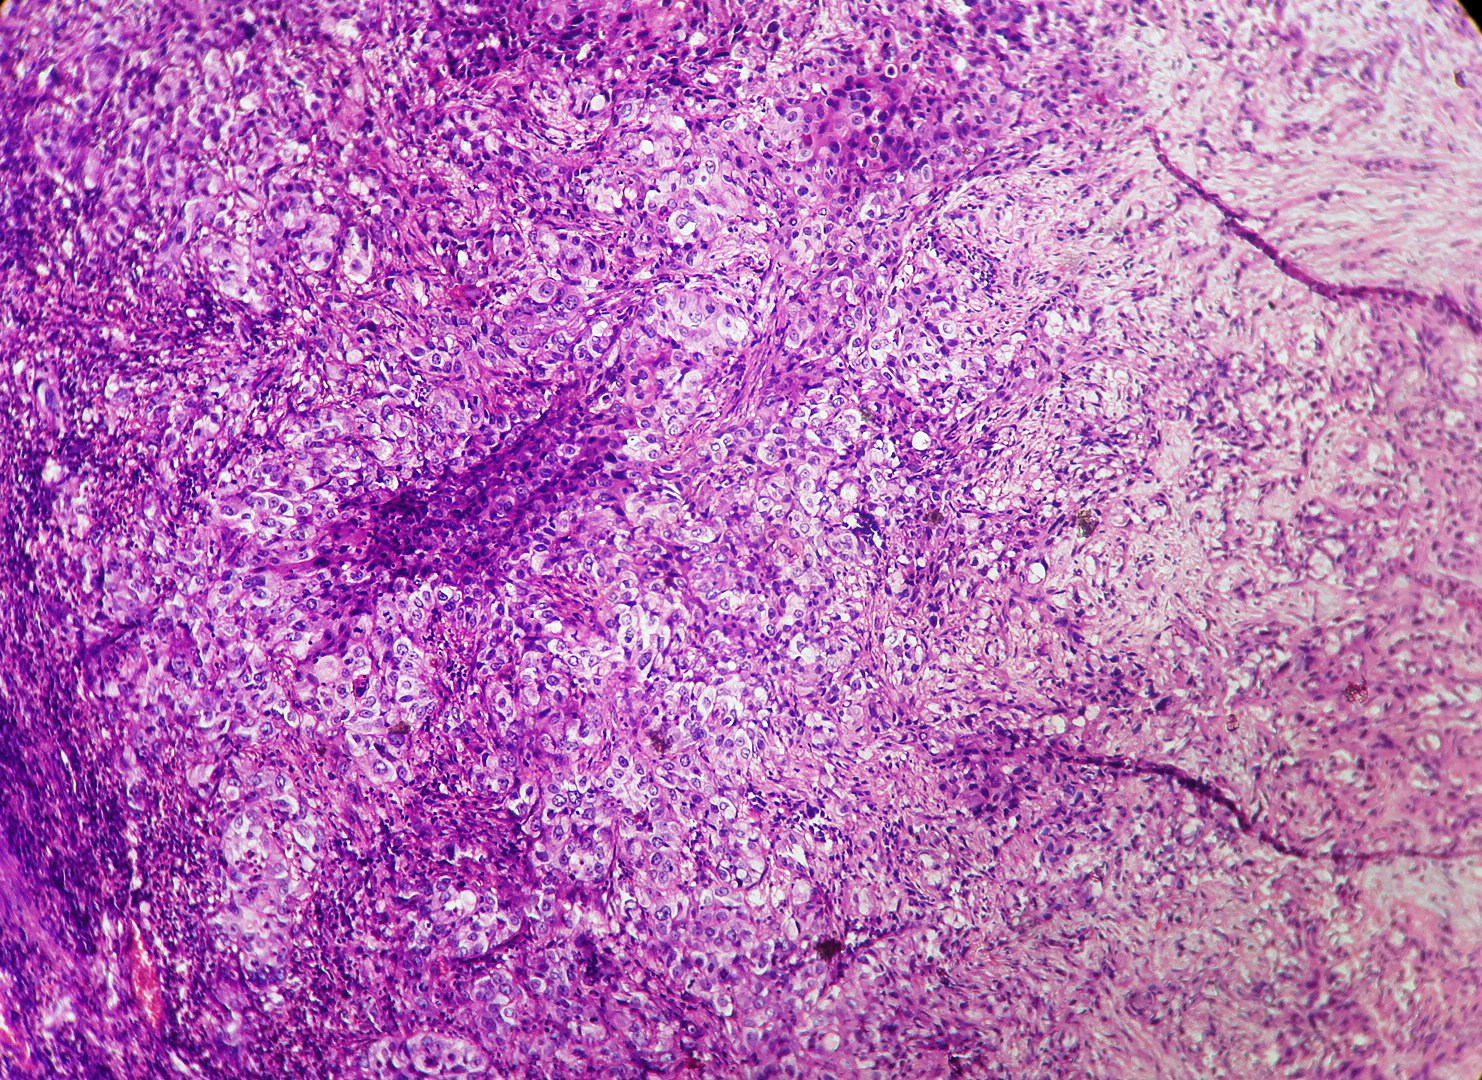

In our study, we made an attempt to evaluate the pattern of tumor growth, its degree of differentiation, progression and associated mucosal changes. In 15 cases of urothelial papilloma, it is characterized by discrete papillary growth with a central fibrovasular core lined by urothelium of normal thickness and cytology (Figure 1). In five cases of Papillary urothelial neoplasm of low grade malignant potential (PUNLMP), histopathologically the tumor is characterized by delicate, orderly, tenuous papillary structures with orderly arrangement of cells within the papillae with minimal architectural abnormalities and nuclear atypia usually limited to basal layer irrespective of cell thickness (Figure 2). The major distinction from papilloma is that in PUNLMP the urothelium is much thicker and nuclei are significantly enlarged. In 21 cases of low grade urothelial carcinoma, histologically it is characterized with papillary axes which are more compact, crowded, fused at the base and lined by unordered cells showing both architectural and cytological abnormalities with frequent mitosis (Figure 3). In 51 cases of high grade urothelial carcinoma showed fused papillary axes over the large areas resulting in sheets and solid areas. The cells have enlarged, hyperchromatic, pleomorphic nucleus in full thickness of the epithelium with increased atypical mitosis (Figure 4). As per TNM staging used in our study we observed majority of the bladder tumours were invasive accounting for 78.25% (Figure 5 & 6) as compared to non-invasive bladder tumours constituting 21.73% of the cases as shown in table 3.